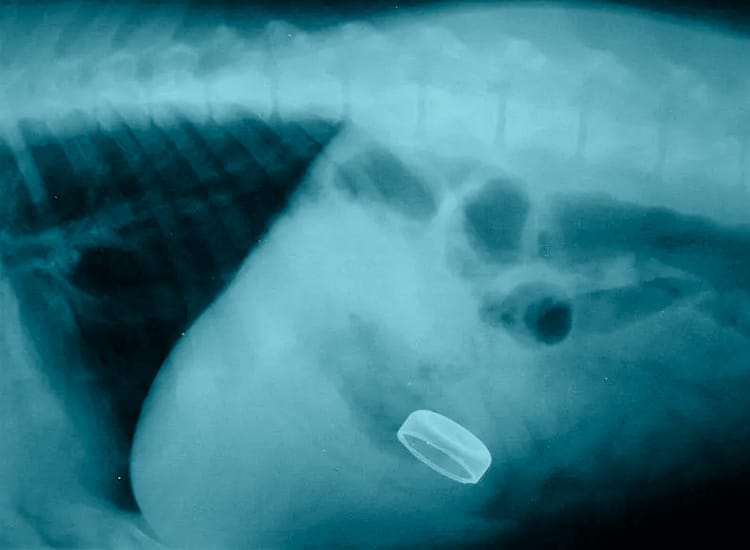

• Une radiographie simple du tube digestif du chien.

L’examen radiographique du tube digestif du chien peut révéler la présence visible du corps étranger si celui-ci est radioopaque (aiguille à coudre par exemple mais s’il s’agit d’un bout de plastique, celui-ci ne se verra pas sur une radiographie simple) ou une forte constipation ou la présence de gaz importants…

Radiographie d’un bouchon logé dans l’estomac d’un chien qui ne sera pas digéré et risque de provoquer une occlusion intestinale